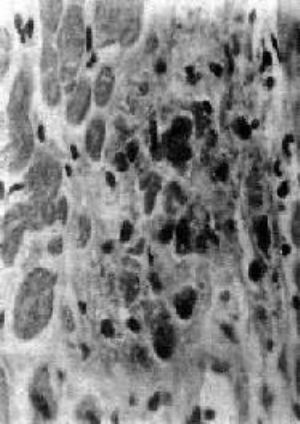

Aschoff 小体体积颇小,一般显微镜下才能看见(图1),多发生于心肌间质、心内膜下和皮下结缔组织;心外膜、关节和血管等处少见。在心肌间质内者多位于小血管旁,略带圆形或梭形,其中心部为纤维素样坏死灶,周围有各种细胞成分:

图1 Aschoff小体

主由Anitschkow细胞、Aschoff巨细胞和淋巴细胞等组成,中心部常有纤维素样坏死物